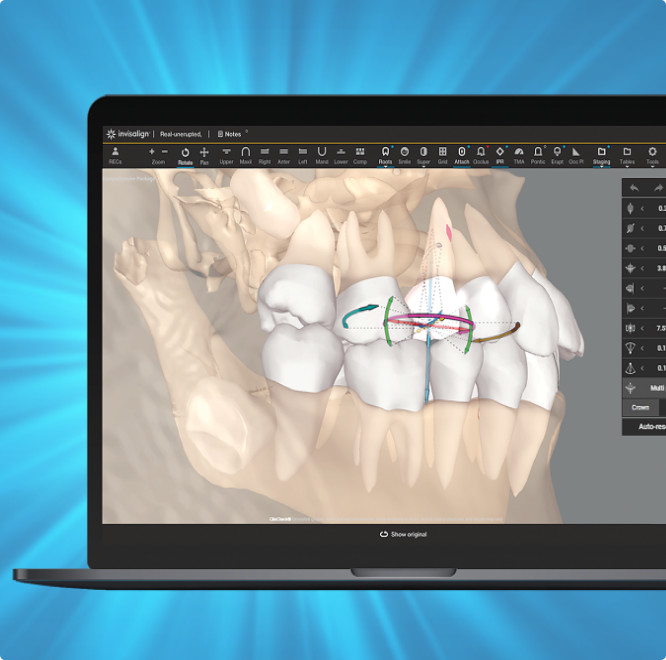

CBCT integration in ClinCheck® Pro software

Auto-generates a 3D model with roots, crown, and bone for more-informed treatment planning.

See patients' roots, crowns, and bone in one auto-generated 3D model with new CBCT integration.

Maximizes the efficiency of powerful ClinCheck tools like 3D Controls.

Shows you real root renderings and bone visualizations based on actual scan data.

Simulates root movement along with tooth movement.

Helps you leverage your expertise across a broad range of clinical indications.

Informs your Invisalign® treatment planning.